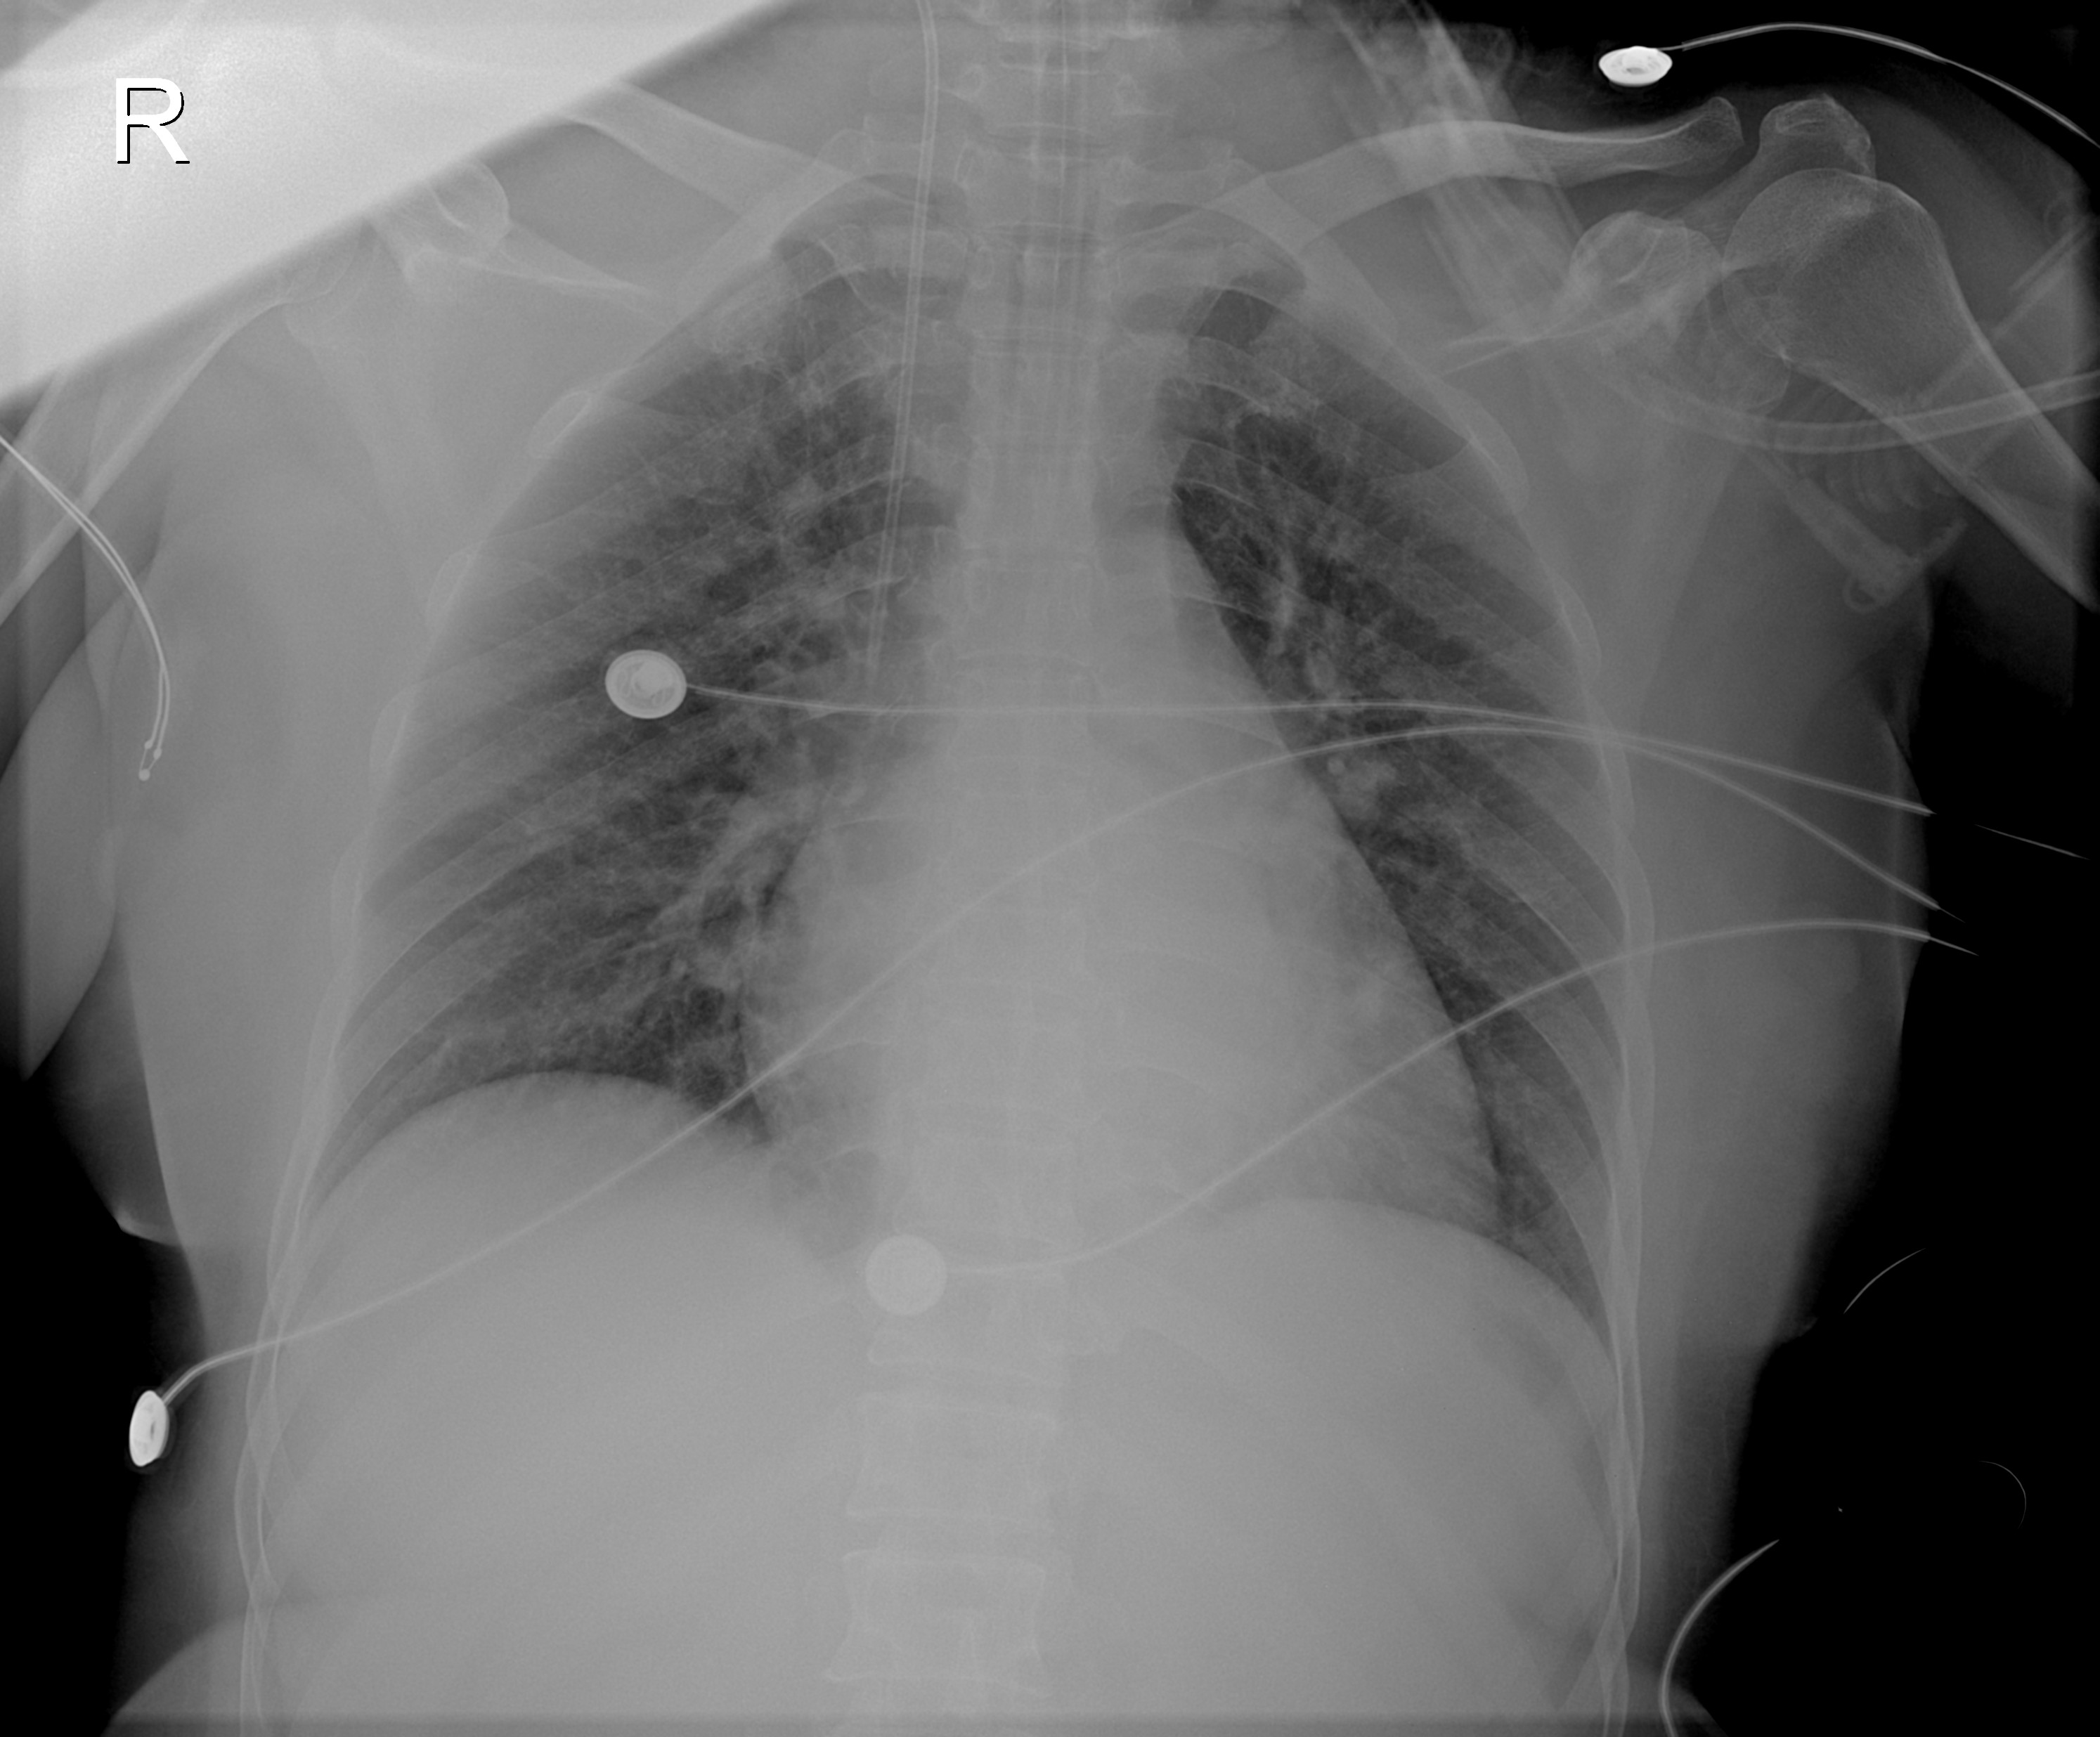

附图4 患者入院3周后胸部CT(2021-07-05)